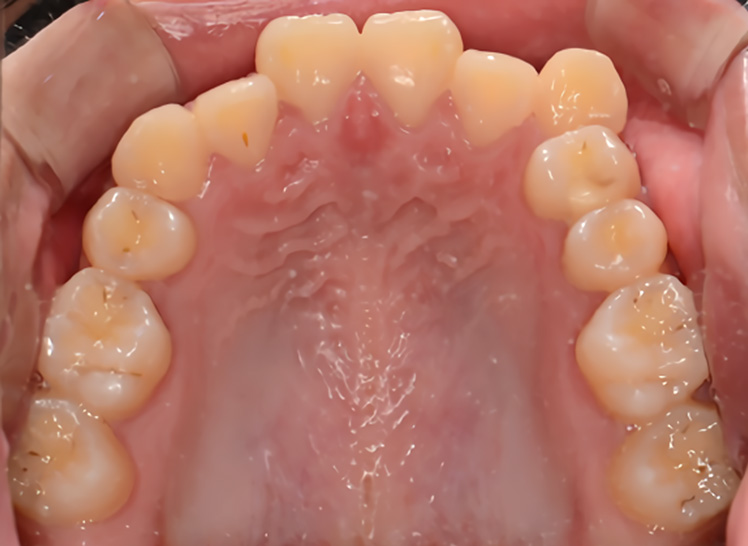

돌출된 입술과 앞니를 개선하기 위해 소구치를 발치하여 공간을 확보한 후

앞니를 안쪽으로 후퇴시켜 자연스러운 입술선과 아름다운 측모를 완성하였습니다.

• 주증상

총생, 입술돌출, 과개교합

• 치료기간

약 2.5년

• 부작용